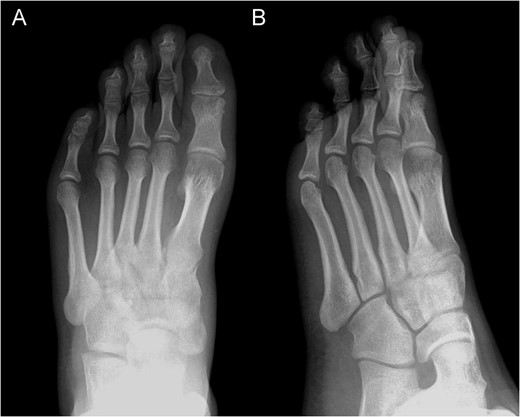

Posterior–anterior X-ray imaging of the left forefoot, showing an intra-articular osteolytic lesion (arrow) in the condyle of the proximal phalanx of the hallux.